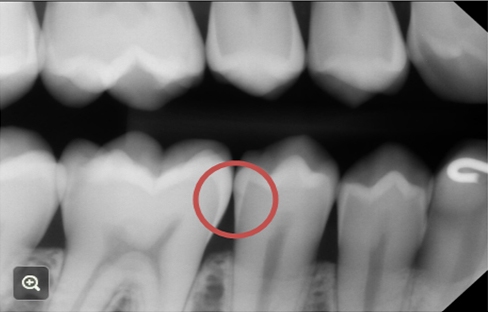

For a more accurate picture of the decay process, I found this x-ray. Look at the area that is circled. The molar on the left has a very superficial caries lesion that is still in the enamel. The premolar on the right has a v-shaped caries lesion that has barely penetrated the enamel and there is a very slight darkening in the dentin.

Incipient caries, as illustrated in the top image on the left or in the x-ray in the molar, can be re-mineralized. There are minerals in your saliva that can deposit in the lesion, strengthening it. But if the white spot lesion has grown and become chalky and soft, which would be the case in the middle image above or the premolar on the x-ray, it is too late and needs to be restored. And, of course, if it has progressed to frank cavitation, as in the above image on the right, it needs to be restored.